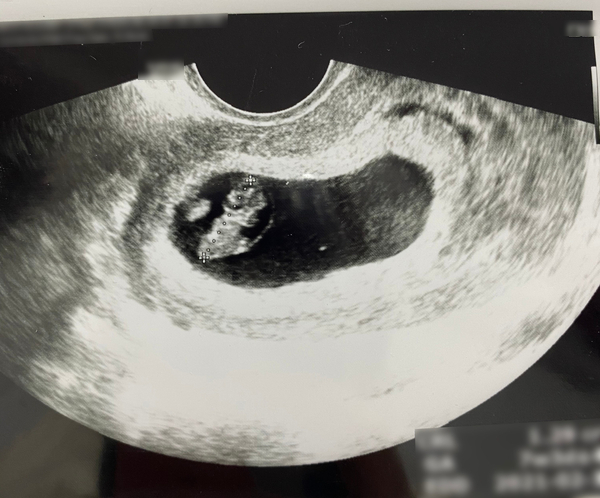

토덧으로 힘든 일상 보내고 있지만 뱃속 사랑이

초음파 사진만 봐도 매 순간 행복 느끼고

있어요

빨리 만나고 싶어 누굴 더 닮았을까

첫째가 아빠 유전 강하단 말도 있고

우리 2세 어떨까 궁굼해요 그 전에